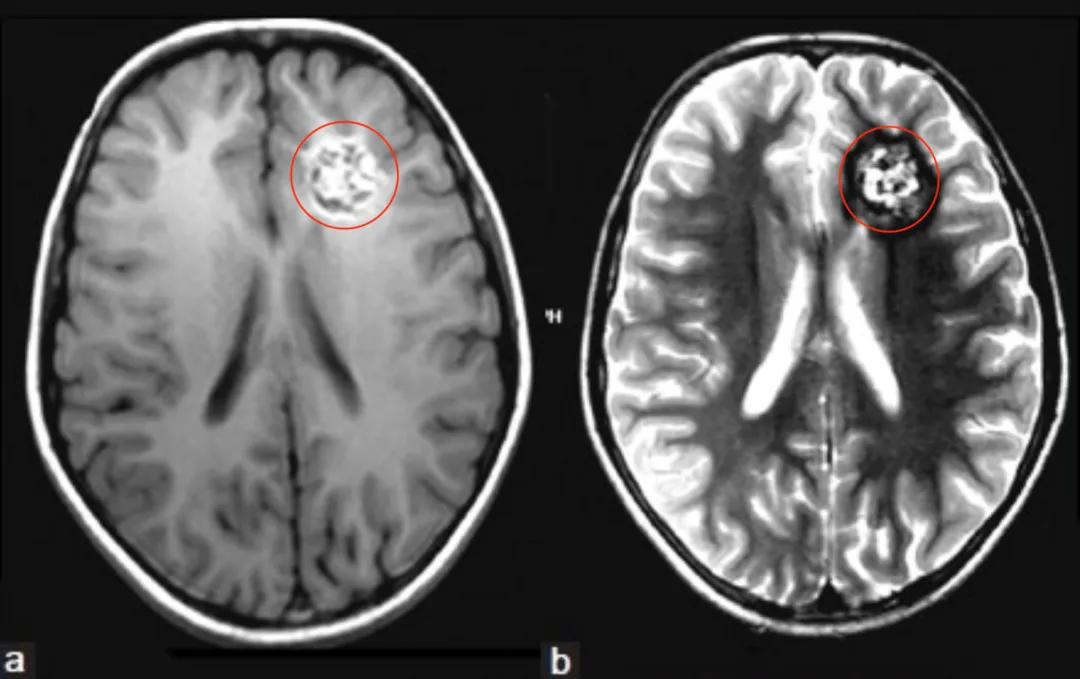

CT检查显示在小琪左侧额叶深部有一个钙化灶,头颅MRI脑T1、T2、FLAIR像显示左额叶深部异质性病变[图2a和b]。根据这些发现,诊断海绵状血管瘤伴顽固性癫痫发作。

更令人吃惊的是,这个血管瘤大小约5×4cm,相当于在孩子脑子里塞了一颗乒乓球大小的异物。